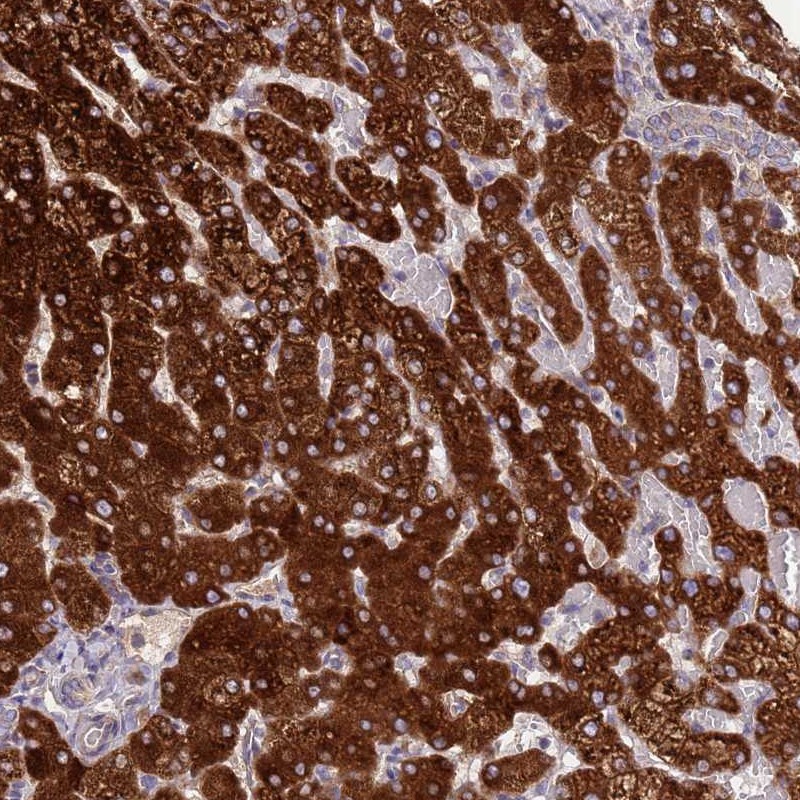

Immunohistochemical staining of human liver shows strong cytoplasmic positivity in hepatocytes.